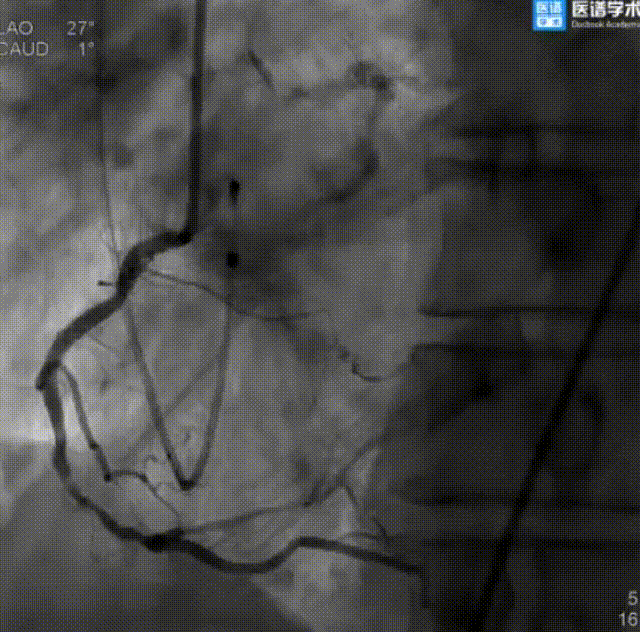

冠状动脉造影+PCI介入治疗:

造影提示左主干严重钙化病变

支架成功释放

支架释放后冠脉造影

患者全麻成功后,先经右股动脉置入6 F动脉鞘管并送入JL 4.0、JR 4.0造影导管行冠状动脉造影。结果显示左主干全程弥漫钙化病变,开口钙化狭窄80%;左前降支近中段全程弥漫钙化病变,最重狭窄70%,D1开口狭窄60%;左回旋支开口狭窄80%,近段弥漫钙化病变,最重狭窄70%;右冠状动脉中段原支架开放良好,支架入口前狭窄30%,远段狭窄70%。

经讨论,决定对LM行PCI治疗,先送入切割球囊至LM开口病变处行预扩张,后送入支架释放,即刻造影结果显示无残余狭窄及夹层,且前向血流TIMI Ⅲ级。